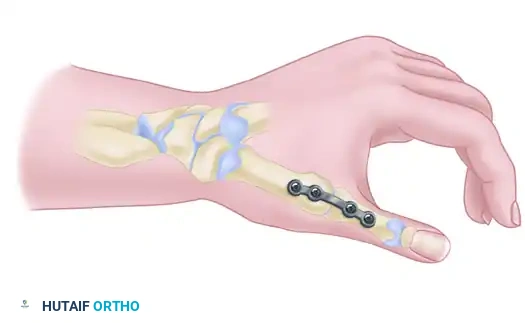

4. Definitive Fixation

Rigid internal fixation is paramount. The surgeon may choose between plate-and-screw fixation or multiple K-wires, depending on bone quality and surgeon preference.

Option A: Plate Fixation (Preferred for Rigid Stability)

With the provisional K-wire in place, contour a 2.4-mm T-plate or a 2.0-mm/2.4-mm minicondylar blade plate (e.g., Synthes USA, Paoli, PA) to the dorsal-radial aspect of the joint. Insert the screws, ensuring at least two (preferably three) screws achieve bicortical purchase in both the metacarpal and the trapezium.

Take extreme care to use image intensification in multiple planes. It is critical to ensure that the screws or blades do not penetrate the adjacent STT joint or the CMC joint of the index finger.